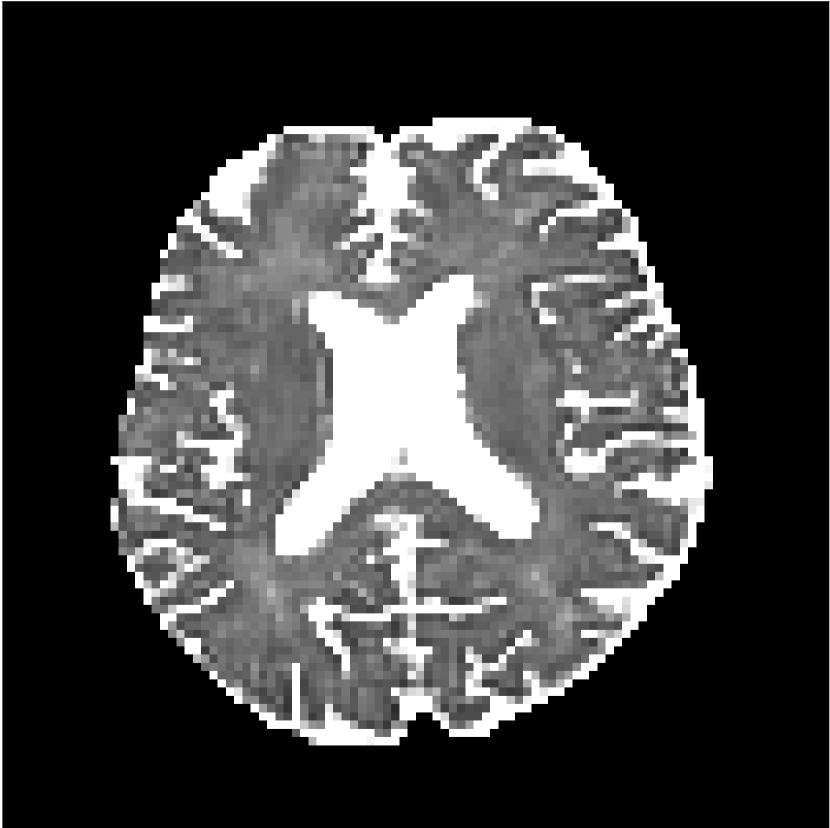

Figure 8 shows examples of non-diffusion-weighted images before and after processing. The raw images (Raw) served as the input for the magnitude deep learning (MCNN) and complex deep learning (CCNN) methods.

Raw

MCNN,

MCNN Resid.,

CCNN,

CCNN Resid.,

No PF

5/8 PF

Both methods remove artifacts, but the MCNN method allows residual rippling artifacts to pass through in the presence of partial Fourier. These rippling artifacts are not present in the CCNN method.